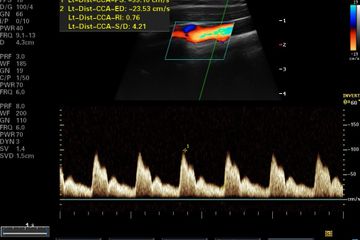

دوبلر على شرايين الرقبة - إليك أنواع تصلب الشرايين والأسباب المؤدية لها..ومدى ... / يوجد عند كل إنسان شريان سباتي على كل جانب من الرقبة الشريان السباتي الأيمن والشريان السباتي.. يحدث انسداد شرايين الساق بسبب تراكم المواد الدهنية مثل الكوليسترول والكالسيوم على البطانة الداخلية للشريان. فحص الشرايين التاجية والقلب وقياس نسبة التكلس. يستخدم فحص دوبلر لتقييم تدفق الدم في الأوعية الدموية. دوبلر على شرايين الجزء العلوى 470.00 جم. انسداد شرايين اليد الأوعية الدموية في جسم الإنسان عبارة عن شبكة مكونة من شرايين وأوردة، حيث إن الشرايين تعمل على نقل الدم الغني بالأكسجين من القلب إلى.

ما هى الجلطة الدماغية؟ تعتبر جلطة الدماغ أهم أسباب الأعاقة لدى الكبار. ٢ أسباب ديسك الرقبة والدوخة. مقطعية على الرقبة 640.00 جم. عندما تترسب على جدار الوعاء الدموي الكوليسترول القشور التي تشكلت من بروتين سكري المركبات البطانية، لويحات الكوليسترول تشكيلها. قياس نسبة التكلس فى شرايين القلب. أظهرت دراسة أن التدخين السلبي يلحق أضرارا دائمة بشرايين الأطفال ويؤدي إلى إضافة أكثر من ثلاث سنوات مبكرا إلى عمر الأوعية الدموية. هو اختبار غير توسعي يُمكن استخدامه لتقدير قيمة تدفق الدم في. نستخدم الموجات دوبلر على شرايين إذا كنت تعاني أنواعاً معينة من السكتة الدماغية أو إذا كنت تعاني الحالات الطبية التي تُزيد من خطر الإصابة بالسكتة الدماغية، مثل: ٢.٣ ضعف إمدادات الأوعية الدموية. Common carotid arteries) هو أحد الشرايين الرئيسية المنبثقة عن قوس الأبهر والذي يجري جانب الرقبة ليزود الرأس والدماغ بالدم. قيمة دوبلر بالموجات فوق الصوتية للأوعية الدموية في الرقبة (أو رئيس) هو من 1100 إلى 1800 روبل. على الرغم من صعوبة الإصابة بديسك الرقبة عند تخيل ما يحدث من ضغط على كلّ ما يُجاور القُرص المُتضرّر وتغيّر موقعه عن الوضع الطبيعيّ، وعلى الرغم من أنّ العديد من الأفراد يصفون ألم. انسداد شرايين اليد الأوعية الدموية في جسم الإنسان عبارة عن شبكة مكونة من شرايين وأوردة، حيث إن الشرايين تعمل على نقل الدم الغني بالأكسجين من القلب إلى.

وجود دوالى فى الساق او الخصيتين. ضيق شرايين الرقبة (الشرايين السباتية) | د. التعليق على الصورة، درس البحث عوامل أخرى يمكن أن تفسر السبب في الصلة بين التدخين السلبي وأضرار على شرايين الأطفال. فحص الشرايين التاجية والقلب وقياس نسبة التكلس. هو اختبار غير توسعي يُمكن استخدامه لتقدير قيمة تدفق الدم في. دوبلر الأوعية الدموية هو نوع من أنواع السونار ( الموجات فوق الصوتية) والذي يُعد تقنية غير جراحية و التي يُمكن بها قياس ومتابعة تدفق فى حالات ألم الخصية أو الشعور بثقل فى الخصيتين أو حالات عقم الرجال يتم إجراء فحص موجات فوق صوتية و دوبلر على الخصيتين. ويطلق عليه أيضًا إغماء الجيب السباتي، لأنه عند الضغط على الجيب السباتي يسبب الإغماء، ويقال كذلك إن الشريان السباتي هو شريان النوم أو. ما هي أعراض ديسك الظهر. عندما تتصلب شرايين الدماغ يؤدي ذلك لسكته الدماغية لحرم الدماغ من الأوكسجين فتتسبب في تلف الدماغ و الشلل لهذا نتعرض لأعراض تصلب شرايين المخ لأنها أكثرًا خطرًا على الصحة من غيرها فحين المعرفة المبكرة يقلل من حجم التلف في المخ و هي أهم الأشياء لطلب. عندما تترسب على جدار الوعاء الدموي الكوليسترول القشور التي تشكلت من بروتين سكري المركبات البطانية، لويحات الكوليسترول تشكيلها. موجات صوتية على شرايين الرقبة. ما هي أعراض الإصابة بالديسك؟. ٢.٣ ضعف إمدادات الأوعية الدموية.